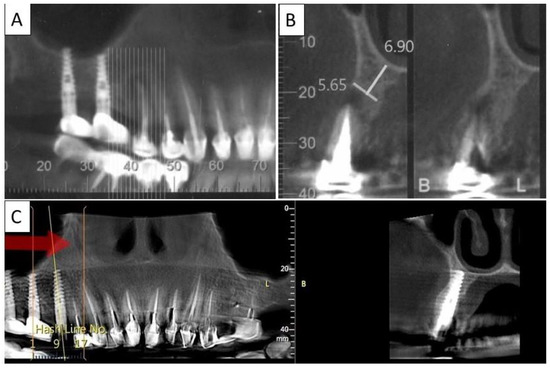

3.3. Case 3

A 62-year-old male patient in good general health condition. Patient presented with tooth 21, vital tooth, horizontal oblique root fracture with associated severe bone loss including loss of buccal cortical plate. Palatal cortical plate remained intact.

Nontraumatic extraction of tooth 21 (Figure 6), followed by bone augmentation using the magnesium membrane shield technique to rebuild the buccal wall as described in Section 2. The implant was immediately covered with a provisional crown due to its location in the aesthetic zone.

Four months post operatively, there was an excellent regeneration of bone defect including a fully regenerated cortical buccal plate (Figure 7). The implant was stable, and a good healing of the soft tissues was observed in the postoperative phase.

Figure 7.

(A) Panoramic CBCT section shows bone loss around tooth 21. (B) Sagittal CBCT section of the area around tooth 21 shows extensive buccal bone loss. (C) A sagittal CBCT section shows the implant placed at site 21 with a restored cortical buccal plate. (D) Panoramic CBCT section shows bone formation around the implant in area 21.